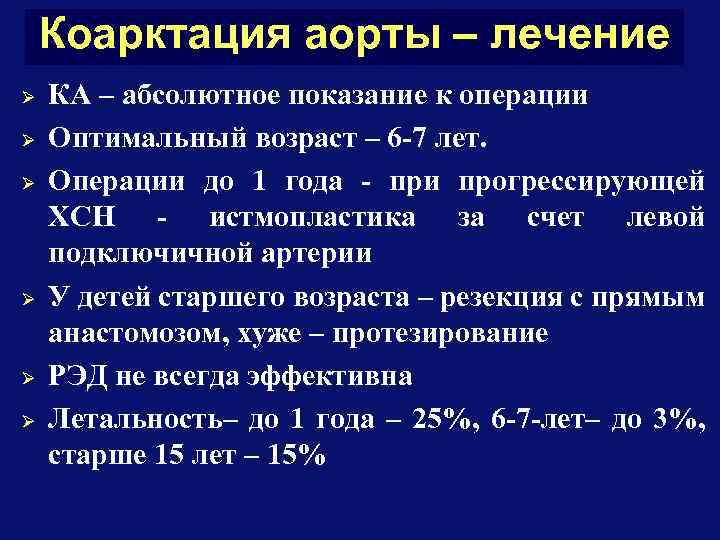

Коарктация аорты – лечение Ø Ø Ø КА – абсолютное показание к операции Оптимальный возраст – 6 -7 лет. Операции до 1 года - при прогрессирующей ХСН - истмопластика за счет левой подключичной артерии У детей старшего возраста – резекция с прямым анастомозом, хуже – протезирование РЭД не всегда эффективна Летальность– до 1 года – 25%, 6 -7 -лет– до 3%, старше 15 лет – 15%